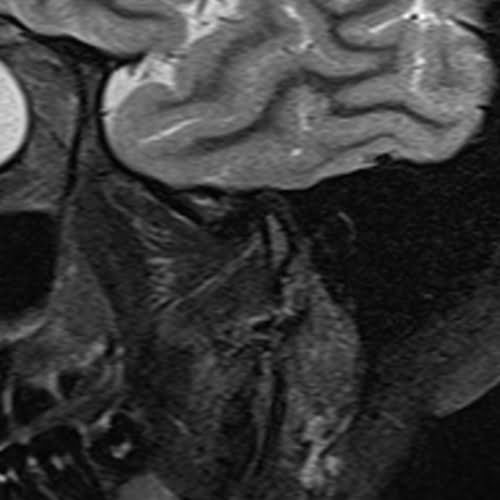

TMJ left side STIR images